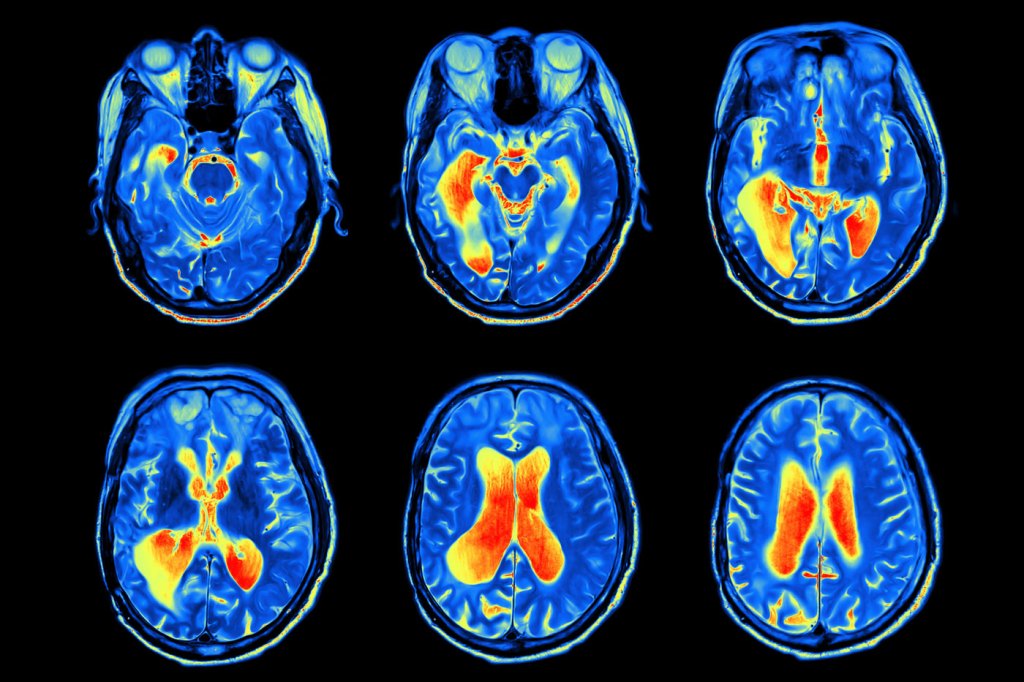

There are a lot of differences between jazz and classical music. But as a Northeastern University professor has discovered, these differences even trickle down to the musicians’ brains.